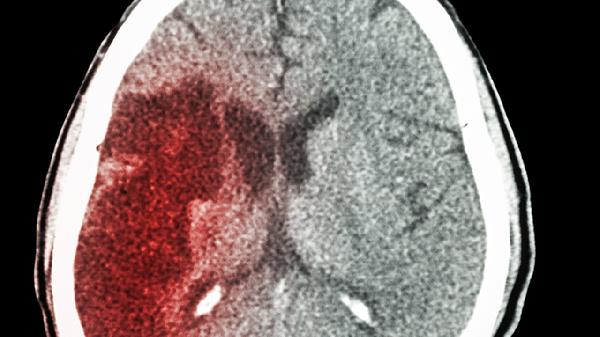

脑出血最严重的并发症及护理措施有哪些

脑出血最严重的并发症主要有脑疝、肺部感染、应激性溃疡、深静脉血栓、癫痫持续状态等。护理措施包括密切监测生命体征、保持呼吸道通畅、预防压疮、康复训练、心理支持等。

脑疝是颅内压急剧升高导致脑组织移位的结果,可能与血肿扩大、脑水肿加重等因素有关,通常表现为意识障碍加深、瞳孔不等大、呼吸节律紊乱等症状。需紧急降低颅内压,可遵医嘱使用甘露醇注射液或呋塞米注射液,必要时行去骨瓣减压术。

脑出血患者护理需注意维持床头抬高30度以降低颅内压,每2小时翻身预防压疮,鼻饲饮食选择高蛋白匀浆膳保证营养。康复期应循序渐进进行肢体被动活动,配合针灸改善肌张力。家属需学习识别瞳孔变化、呕吐等危险信号,避免情绪刺激诱发血压波动。定期复查头颅CT评估血肿吸收情况,长期服用阿托伐他汀钙片预防复发。